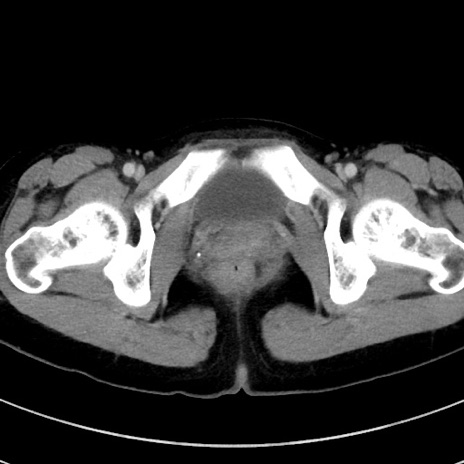

症例17(横断像)

【症例】20歳代女性

【主訴】嘔吐、下腹部痛

【現病歴】昨日夕食後に嘔吐し下腹部痛が出現。本日になっても嘔吐持続し改善しないため来院。

【身体所見】意識清明、BT 37.2℃、BP 108/67mmHg、腹部:平坦、やや硬、下腹部正中から右にかけて圧痛あり、反跳痛軽度あり、tapping pain(+)。

【データ】WBC 13600、CRP 14.94